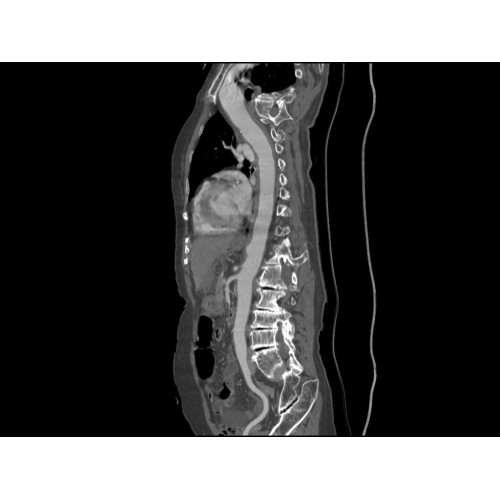

Компьютерный томограф GE Brivo CT385 представляет собой современное диагностическое оборудование, сочетающее высокую точность исследований с повышенным комфортом для пациентов. Этот аппарат открывает новые возможности для детальной визуализации анатомических структур.

Позволяет проводить комплексные исследования всех анатомических зон, включая нейровизуализацию, ангиографию, исследования органов грудной и брюшной полости. Особенно эффективен для раннего выявления онкологических заболеваний.

Обеспечивает высокую точность при кардиологических исследованиях, визуализации костных структур и суставов. Подходит для динамического наблюдения в ходе лечения.